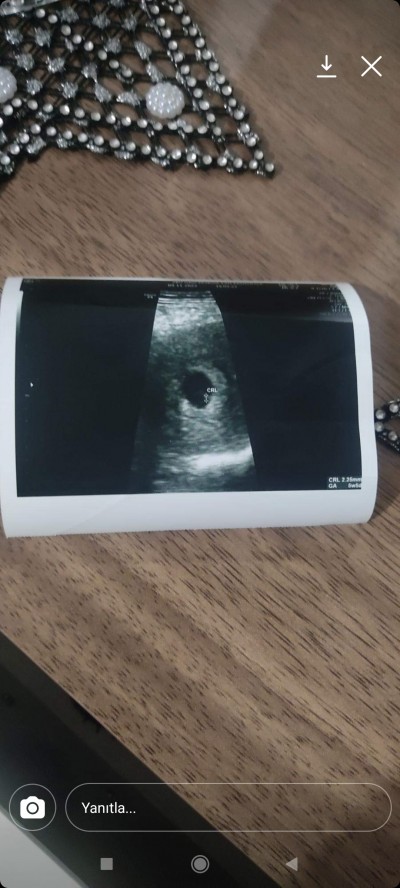

Merhaba arkadaşlar keseye göre cinsiyet tahmini yapabilirmisiniz sadece merak ediyorum bu arada 10 haftalık hamileyim

image